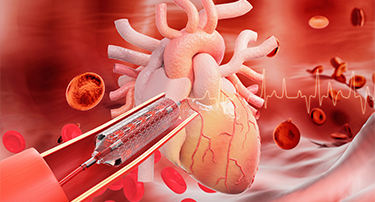

Heart Bypass Surgery Cost in Jaipur, India: A Complete Guide

Heart bypass surgery is a type of surgery that creates a new path for blood to flow when your heart’s arteries are blocked. Cardiologists usually take a healthy blood vessel from your chest or leg and connect it around the blocked artery.

A Complete Guide to Heart Bypass Surgery: Why It’s Done, How It Works & What to Expect

Heart bypass surgery, or coronary artery bypass grafting (CABG), is a life-saving surgery that is done to enhance the flow of blood to the heart when the coronary arteries are blocked or narrowed very much. Such a condition, or coronary artery disease (CAD), may result in chest pain (angina), shortness of breath, and a higher risk of heart attacks.

Heart Bypass Surgery: Purpose, Procedure, Risks And Recovery

Heart bypass surgery, also called CABG, is a critical surgical procedure used to ensure adequate blood flow to the heart when the coronary arteries have blockages or are narrowed with coronary artery disease (CAD). Blockages in the coronary arteries reduce the oxygen supply to the heart. This can result in chest pain and shortness of breath, and may even lead to heart attacks, which can be fatal. This surgical procedure is often recommended when lifestyle modification, drugs, or other minimally invasive treatments do not respond to the condition.